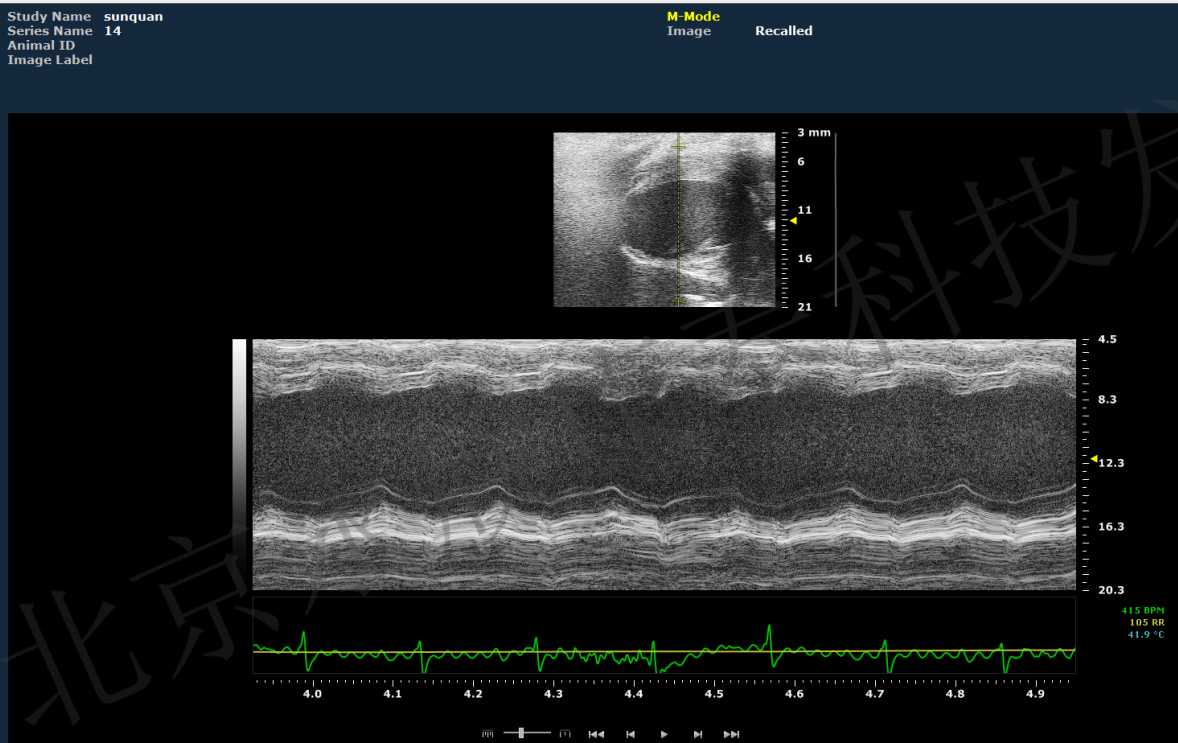

4、动物心脏超声及数据分析